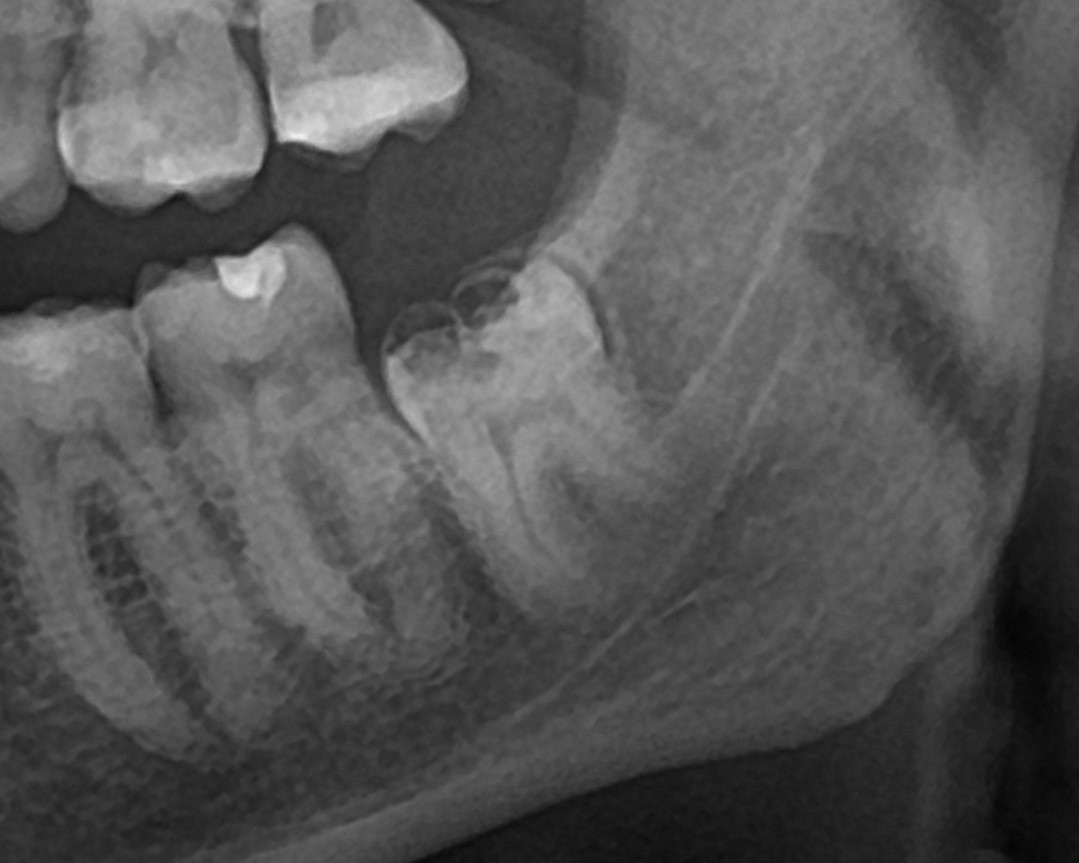

Пациент обратился с жалобами на дискомфорт и болевые ощущения в области зуба мудрости. На снимке видно дефект коронковой части, это не кариес, а дисплазия эмали.

диагностическая ОПТГ

Удаление данного зуба представляло высокий риск из-за возможного повреждения нижнечелюстного нерва, что могло привести к онемению нижней губы, подбородка.